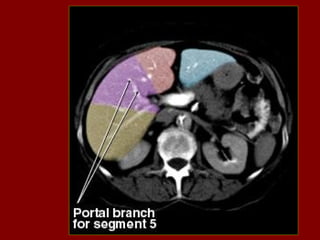

PB Corpo do pâncreas PC Confluência portal PF Gordura perirrenal PH Cabeça do pâncreas PS Músculo psoas PT Cauda do pâncreas PU Processo uncinado do pâncreas PV(R) Ramo direito da veia porta QL Músculo quadrado do lombo R Costela RA Músculo reto do abdome RC Pilar direito do diafragma RF Gordura retroperitoneal RG Glândula supra-renal dir. RHV Veia hepática direita RIL Lobo inf. do pulmão dir. RK Rim direito RL Lobo direito do fígado RP Pelve renal RPV Veia porta RRA Artéria renal direita E RRV Veia renal direita RU Ureter direito S Processo espinhoso SA Artéria esplênica SC Medula espinal Sp Baço SF Flexura esq. do colo St Estômago SI Intestino delgado SV Veia esplênica SMA Artéria mesentérica sup. Tc Coto transverso SMV Veia mesentérica sup. TVP Processo transverso Xp Processo xifóide